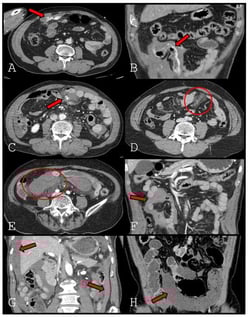

Background: Delayed bowel ischemia is a major cause of failure of nonoperative management in patients with blunt mesenteric injury. Although decreased bowel wall enhancement on computed tomography (CT) is a definitive sign of bowel ischemia, it is uncommon and may be absent on early imaging. This study aimed to identify specific CT findings that predict bowel ischemia to distinguish patients requiring surgery from those suitable for conservative management. Methods: We retrospectively reviewed 174 patients with blunt mesenteric injury treated at a Level 1 trauma center between January 2013 and December 2024. Initial CT findings were classified as mesenteric contrast extravasation freely extending into the peritoneal cavity (extravasation type 1), contrast extravasation tracking along the bowel contour (extravasation type 2), pseudoaneurysm, mesenteric haziness, mesenteric hematoma, interloop fluid, dependent portion fluid, and decreased bowel wall enhancement. Predictors of bowel ischemia were evaluated using univariate analysis and ridge-penalized multivariable logistic regression. Results: Bowel ischemia occurred in 30 patients (17.2%). Decreased bowel wall enhancement was rare (4.6%) but demonstrated perfect specificity and positive predictive value (both 100%), with low sensitivity (26.7%). Extravasation type 2 showed high specificity (97.2%) and remained an independent predictor of bowel ischemia. Dependent portion fluid showed relatively high sensitivity, whereas mesenteric haziness and mesenteric hematoma were inversely associated with ischemia. Conclusions: Contrast extravasation tracking along the bowel contour and decreased bowel wall enhancement on early CT are strong predictors of bowel ischemia in patients with blunt mesenteric injury. These findings should prompt consideration of early surgical exploration, even in patients who initially appear hemodynamically stable.